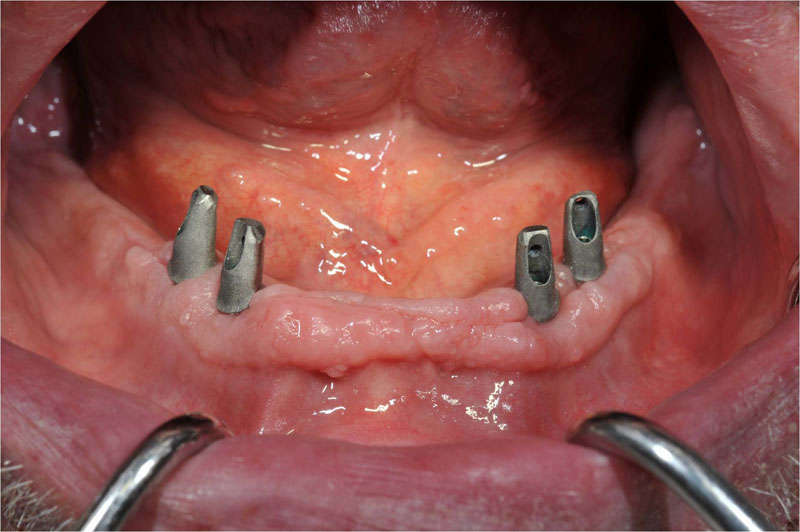

Unterkiefer Stegversorgung

| Hier bieten vier Implantate eine relativ einfache Möglichkeit eine Prothese mit zwei Riegeln optimal zu befestigen. Diese sind an der Prothese im geöffneten Zustand deutlich zu sehen, geschlossen bleiben sie selbst im Spiegelbild des Mundinnenraumes unsichtbar. Sie vergessen alle Druckstellen und Ängste und freuen sich endlich wieder einmal richtig abbeissen zu können! |